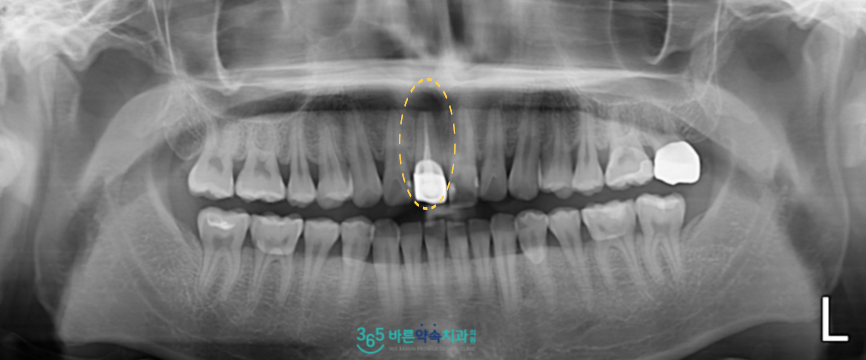

정밀한 검사를 위해

파노라마 사진을 촬영해 보았더니

위턱 오른쪽 첫 번째 앞니(#11)의

뿌리 끝에 염증이 생긴 것을

확인할 수 있었습니다.

예전에 신경치료를 받고

보철물 수복까지 마무리된 치아이지만

현재 뿌리 끝 치근단 부위에

염증이 생긴 것인데요.